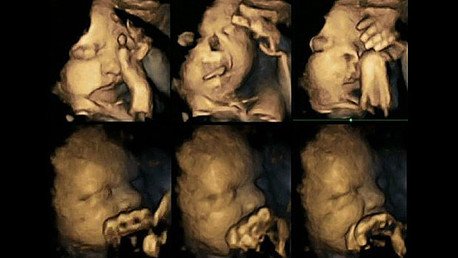

La doctora Nadja Reissland, del departamento de Psicología de la Universidad de Durham, Reino Unido, y directora del estudio, ha examinado las ecografías 4D de 20 mujeres, informa el diario 'The Times'.

Según los resultados, los fetos cuyas madres consumen tabaco se tocan la boca y el rostro con mucha más frecuencia que los fetos de las madres no fumadoras. La médica explica que los fetos de madres no fumadoras suelen mover la boca y tocarse la cara cada vez menos a medida que adquieren más autocontrol, es decir, cuanto más se desarrollan, mientras que los fetos de las madres fumadoras mantienen el hábito durante más tiempo. Esto significa que los científicos han obtenido pruebas de que el consumo de tabaco durante el embarazo aumenta el riesgo de provocar retrasos en el desarrollo del bebé.